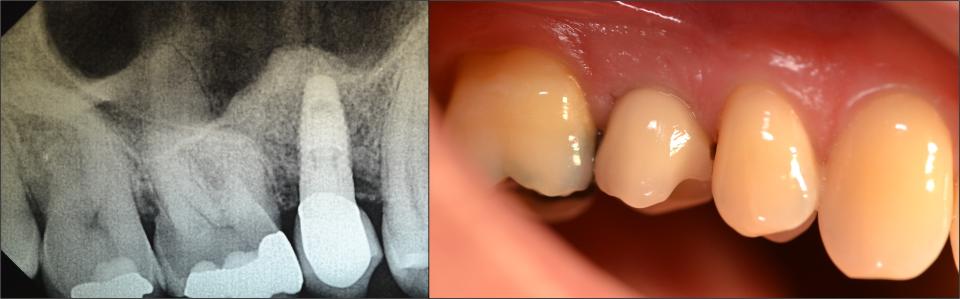

Erfreulicherweise zeigte sich nach neun Monaten eine Verdichtung des Augmentates, so dass im November 2010 eine komplikationslose Implantation eines Nobel Replace Select Tapered Implantates 4,3 x 10 mit 35 Ncm Eindrehmoment gelang. Da dabei noch ein kleiner crestobukkaler Defekt, der sich innerhalb der Kontur des Alveolarfortsatzes befand, mit Knochenmaterial BioOss grün und Bio Gide Membran augmentiert wurde, erfolgte eine gedeckte Einheilung. Die Titannägel wurden bei diesem Eingriff entfernt. Nach einer Woche wurden die Nähte entfernt, der Bereich verblieb weiter ohne provisorische Versorgung.

Im April 2011 erfolgte die Freilegung des Implantates mit Abformung und Anfertigung einer definitiven Krone aus verblendetem Zirkondioxyd auf Titanabudment (Nobel Esthetic). Die Zementierung der Krone auf dem Titanaufbau erfolgte mittels Glasionomerzement. Im ersten Jahr erfolgte ein Recall drei, sechs, neun und zwölf Monate nach Eingliederung des definitiven Zahnersatzes.

Diese Versorgung ist mittlerweile über 12 Jahre in situ bei stabilen Verhältnissen. 2014 kam es zu einer Keramikabplatzung, der Patient wollte aber keine Neuanfertigung durchführen lassen. Er befindet sich weiter im jährlichen Recall.